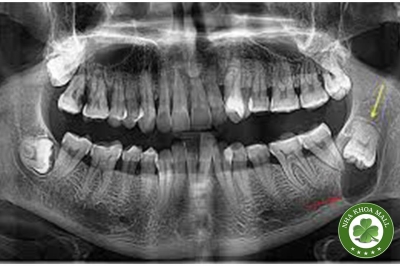

Phát hiện bất thường tình cờ trên phim X-quang toàn cảnh không phải hiếm gặp trong thực hành lâm sàng. Tuy nhiên, khi tổn thương nằm tại vùng khớp thái dương hàm (TMJ) và biểu hiện dưới dạng nhiều khối cản quang, bác sĩ nha khoa cần có cách tiếp cận chẩn đoán hệ thống, phân biệt đúng bản chất tổn thương và đưa ra quyết định xử trí phù hợp. Bài viết này phân tích chuyên sâu một ca lâm sàng điển hình ở bệnh nhân cao tuổi, đồng thời cung cấp khung chẩn đoán và chiến lược theo dõi – điều trị dựa trên bằng chứng.